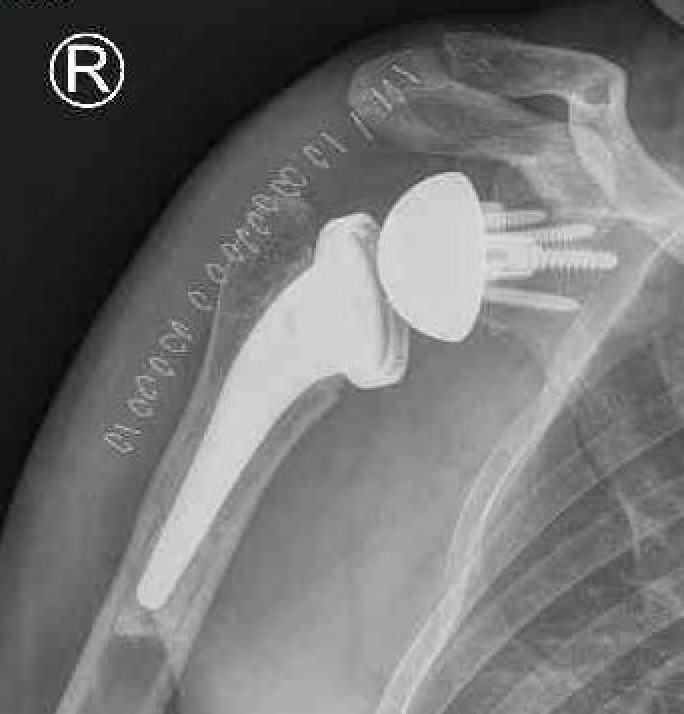

Reverse shoulder arthroplasty

Reverse

- socket in proximal humerus

- ball in glenoid

- center of rotation shifted medially and distally

- allows deltoid to apply compressive force and stabilize joint in absence of rotator cuff

Paul Grammont in 1985

- humeral component concave

- glenoid component / glenospere convex

- glenoid component uncemented with peripheral screws and central plug

- center of rotation shifted medially to glenosphere with humerus distal